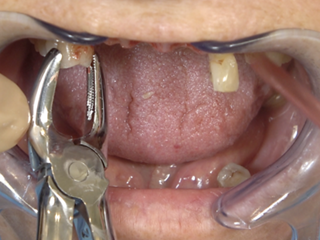

• Initial clinical situation (retracted view).

• Strategic extractions for guide seating on anchor teeth.